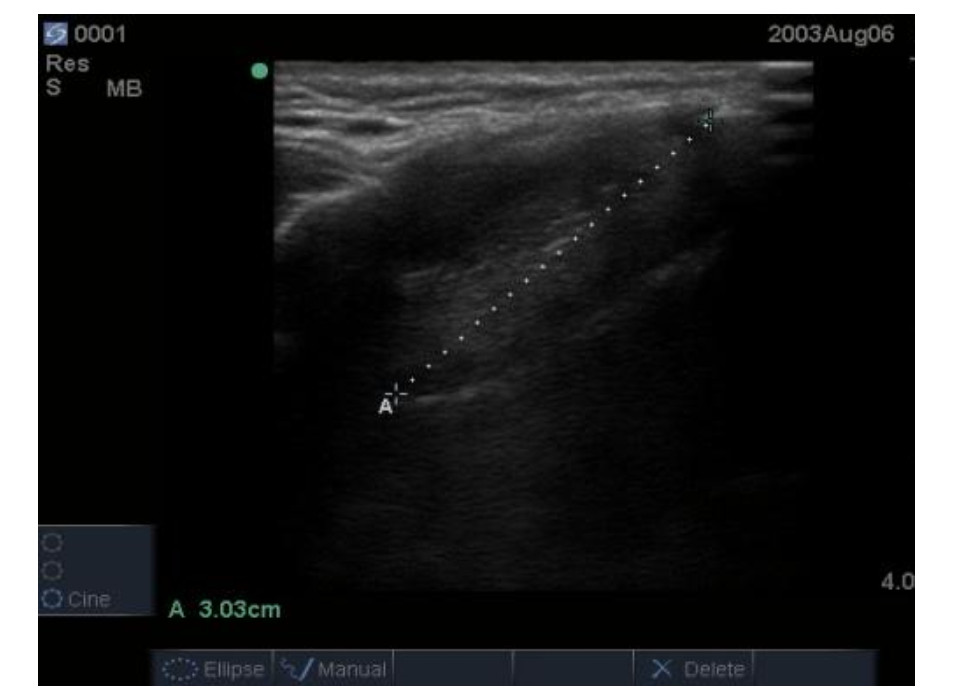

患者术后转入复苏室苏醒,清醒拔管后统一由具备10年以上临床麻醉经验及气道超声评估经验的麻醉医生(对分组情况完全盲态,且本研究所有测量及数据记录工作均由该医生独立完成)进行常规气道评估:张口度(mouth opening, MO)、甲颏间距(thyromental distance, TMD)、颈围(neck circumference, NC)、改良Mallampati分级(modified Mallampati classification, MMT)。之后由其继续进行超声气道指标的测量,患者取平卧、头后仰位,采用索诺声便携式彩超M-Turb(富士胶片索诺声股份有限公司、美国华盛顿州博塞尔市、美国)高频线阵探头测量会厌长度(length of the epiglottis, LE)、真声带长度(length of the true vocal cord, LV)、LE/LV、皮肤到真声带下缘的距离(distance from the skin to the inferior margin of the true vocal cord, DSIV)、皮肤到声带前联合的距离(distance from the skin to the anterior commissure of the vocal cords, DSAV)、DSAV/DSIV。具体测量方法如下:LE:线阵探头横置于患者下颌中线处平行下滑,在短轴平面找到低回声会厌结构。以中线为中轴逆时针旋转,可见会厌长轴平面结构,测量会厌的起点和终点之间的直线距离(图 1A)。LV:超声扫查侧方位甲状软骨侧板,将探头横置于一侧甲状软骨板上,测量真声带长度(图 2A)。DSIV:超声测量皮肤到真声带下缘的距离(图 2B)。DSAV:超声测量皮肤到声带前联合的距离(图 2C)。

| 注:A线为LV;B线为DSIV;C为DSAV 图 2 真声带侧板水平超声图像 Fig 2 Ultrasound image at the level of the vocal fold lamina propria |